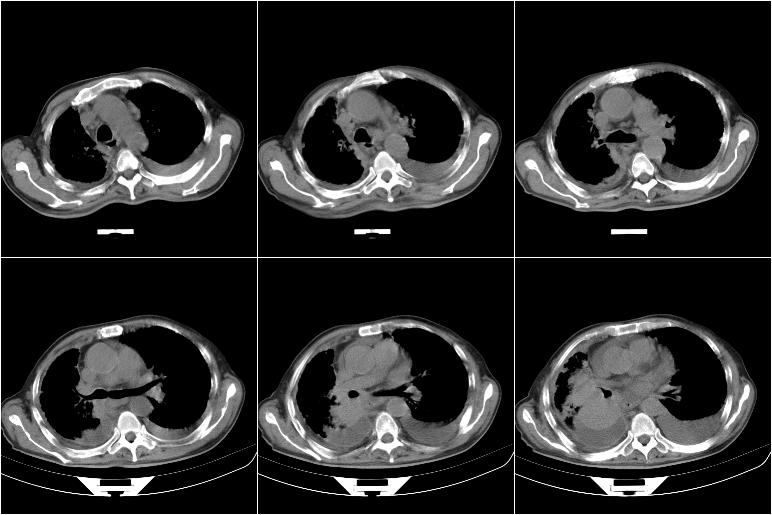

以下是引用边生丽在2009-8-17 11:43:00的发言:[br][br] [br] 右肺中心型癌伴右肺下叶不张、双肺转移并癌性淋巴管炎、心包和双侧胸腔积淮(转移?)、脑转移、肝转移、多骨(颅骨、椎骨)转移。 [br] [br]

以下是引用随光逐影在2009-8-17 14:09:00的发言:[br]支持 右肺中央型癌伴右肺下叶肺不张,纵隔淋巴结转移,双肺转移并癌性淋巴管炎,心包和双侧胸腔积液,脑转移、肝转移、多发性骨(颅骨、脊椎)转移。